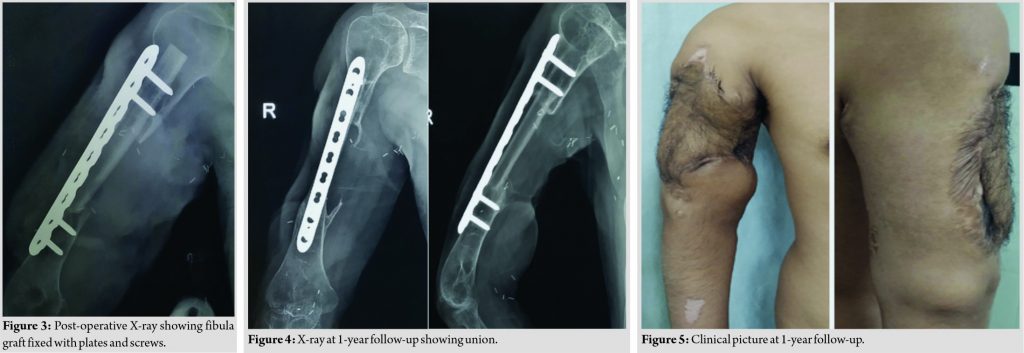

Surgical technique involved approach of both upper and lower limbs simultaneously, with the patient in the supine position. The humeral approach was based on the previous incisions and soft-tissue defects. For non-union, necrotic bone was resected and debridement done, the ends were reamed sequentially to open the canal and to allow the fibula to go inside the humerus medullary cavity. The brachial vessels were identified for anastomosis. The osteomyocutaneous fibular graft was based on the peroneal vessels. The harvested flap included skin paddle, fibula, skin perforators (majority present on the inferomedial part of the fibula), and the peroneal vessels with the venae comitantes. A length of 16 cm and a width of 12 cm of skin flap were harvested along with 9.5 cm of fibula bone. The graft was inserted 2 cm at each end into the humerus, and then, the entire construct was fixed with a 4.5 mm low contact dynamic compression plate with two screws on either side getting four cortex purchase. The peroneal artery was anastomosed end-to-side with the brachial artery. The skin margins of the flap were fashioned accordingly and were sutured to the surrounding skin (Fig. 2, 3). Postoperatively, flap was closely monitored for vascularity and viability and the fixation was protected by a U slab, which was later converted into a functional humerus brace. Physiotherapy started with range of motion and followed by muscle strengthening. Serial X-rays were taken to assess bone union at 6 months and 1 year (Fig. 4, 5).

Case Report: This is a report a case of a 27-year-old male presented with a history of road traffic accident with Gustilo-Anderson Grade 3 B open fracture of humerus midshaft. He developed humerus osteomyelitis, for which he underwent surgical debridement. He presented to us with gap non-union with segmental bone loss. The overlying skin was scarred and had significant limb shortening. Treatment options for such a case are reconstruction or amputation. Challenges for reconstruction were to deal with the segmental bone loss and the soft-tissue defect following scar excision. We tackled both these challenges with an osteomyocutaneous fibula flap. At 1-year follow-up, the humerus showed union and flap uptake was good.